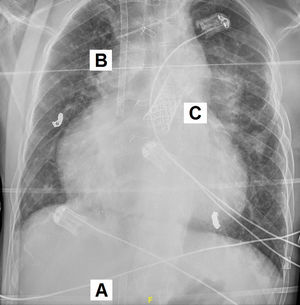

Hombre de 33 años con síndrome de Rendu-Osler-Weber y estenosis aórtica congénita corregida con cirugía de Ross. Presentaba estenosis grave del homoinjerto con implante transcatéter de prótesis pulmonar Melody (Medtronic, Mineápolis, MN, EE. UU.), e hipertensión pulmonar poscapilar grave mixta con disfunción ventricular derecha severa, siendo incluido en lista de trasplante cardiopulmonar. Ingresó por insuficiencia respiratoria, que requirió ECMO veno-venosa percutánea. En la figura 1 se aprecia la cánula de drenaje femoral en la cava inferior (A), la de retorno yugular en la aurícula derecha (B), y la prótesis Melody en la arteria pulmonar (C). Se precisó hemodiafiltración por fallo derecho. Al quinto día se decidió el cambio a cánula de doble luz ProtekDuo (LivaNova, Londres, Reino Unido) como asistencia derecha con oxigenador puente al trasplante cardiopulmonar. En la figura 2 se observa la cánula ProtekDuo (D) atravesando la prótesis Melody (C), con el drenaje en la aurícula derecha y el extremo distal de retorno en la arteria pulmonar. Se retiró la hemodiafiltración a la semana. Realizaba rehabilitación en espera del trasplante. No obstante, presentó sangrado digestivo incoercible, siendo exitus a las 2 semanas.